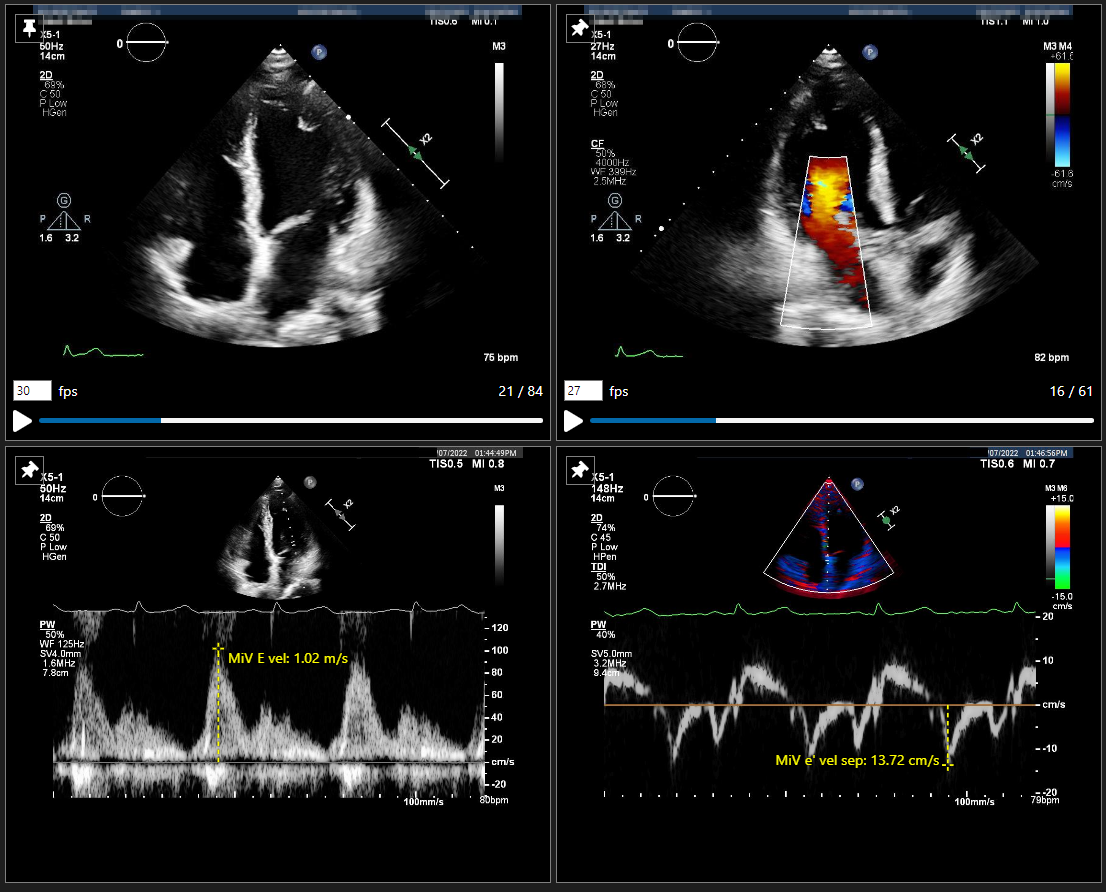

• AIを用いて心エコー画像を解析したい

• EF、Strain (GLS )、ガイドラインに準拠したパラメータをまとめて解析したい